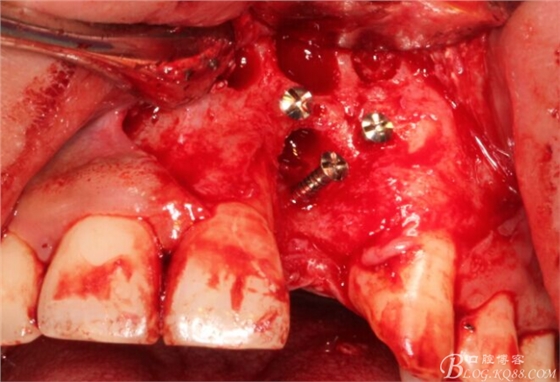

先行粘骨膜減張,取自體血液。

根方用取骨鉆取自體骨。

旋入一長(zhǎng)兩短3顆鈦釘。

將自體骨與BIO-OOS骨粉混合植到術(shù)區(qū),蓋生物膜。

縫合。